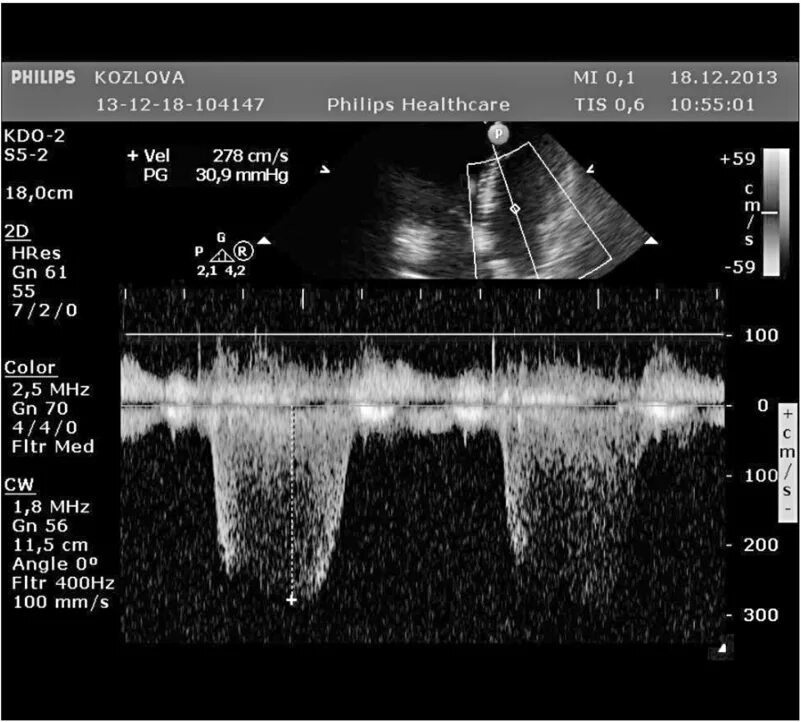

Градиент давления легочной